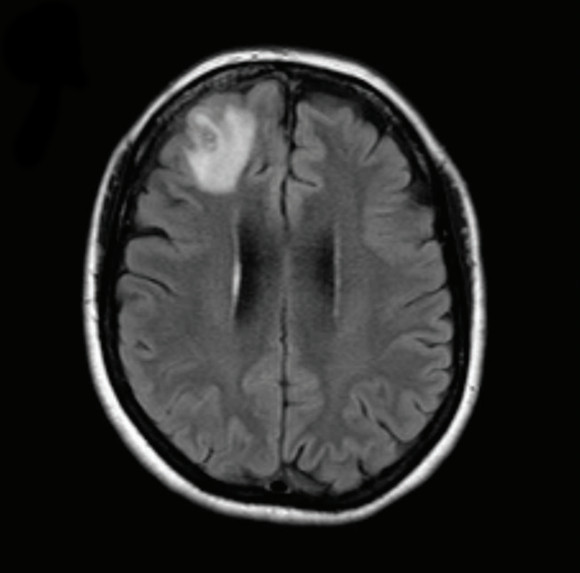

נראה שהפעם הטיפול עזר. מאמצע 2021 ועד תחילת 2022 תוצאות בדיקות הדם השתפרו מאוד וכך גם התסמינים שלה, לפחות כל עוד המשיכה ליטול סטרואידים. אך השמחה הייתה קצרת מועד. במהלך שלושה חודשים האישה, שסבלה בעבר מדיכאון, פיתחה שוב דיכאון וגם בעיות זיכרון. בדיקת MRI של מוחה מצאה באוּנה המצחית הימנית, בחלק הקדמי של קליפת המוח, נגע. וכך הגענו חזרה ליוני 2022 ולתולעת שבנדי שלפה.

בדיקת MRI של מוחה מצאה נגע באוּנה המצחית הימנית. תמונה מה-MRI, עם הנגע בפינה השמאלית העליונה | מתוך המאמר, Hossain M. et al., Emerg Infect Dis. 2023